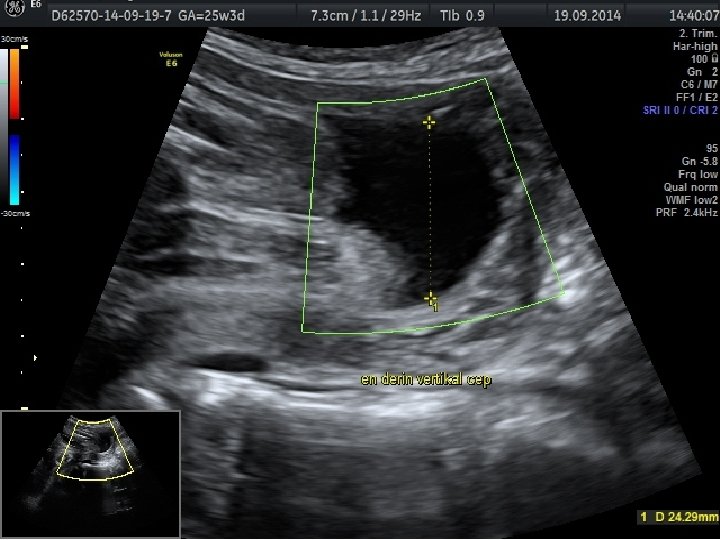

FETAL BÜYÜME BOZUKLUKLARINDA TAKİP VE DOĞUM • Günlük pratikte gelişme gerilikli fetusların takibi, ultrasonografi ile fetal biyometri ve amniyotik sıvı miktarının belirli aralıklarla ölçülmesi ile ve nonstres test veya biyofizik profil gibi antepartum fetal iyilik hali testleri ile yapılmaktadır. • Plasental yetmezliğe bağlı gelişen fetal gelişme geriliğinde standart fetal izlem ile birlikte fetal arterial/venöz dolaşımın Doppler değerlendirmesinin nonstres test ve biyofizik profili ile birlikte kullanımının daha iyi fetal sonuçlar ile ilişkili olduğu gösterilmiştir.

Obstetrik Doppler Ultrasonografi • Umblikal arter Doppler’i en yaygın olarak kullanılan fetal Doppler değerlendirmesidir ve en fazla kullanılan Doppler parametresidir. • Orta serberal arter Doppler • Umblikal arter Doppler değerlendirmesinde direnç artışı, diyastol sonu akımda kayıp veya ters dönme saptanması , artmış perinatal mortalite hızı ile ilişkili olmakla birlikte fetal gelişme geriliği olgularında doğum zamanlamasının belirlenmesini de etkilemektedir.

• Fetal gelişme geriliğinde doğum zamanlaması hakkında iki strateji öne sürülmüştür: 1) izole fetal gelişme geriliği olan olgularda 38+0 -39+6 gebelik haftasında doğum 2) ek risk faktörü olan fetal gelişme geriliği olan olgularda 34+0 -37+6 gebelik haftasında doğum (oligohidramnios, anormal umblikal arter Doppler bulgusu, maternal risk faktörleri gibi)